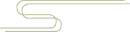

再来熟悉一下骨质疏松症的诊断:

骨质疏松症诊断需依靠临床表现、骨量测定、X 线片及骨转换生物化学指标等综合分析判断。

部分骨质疏松患者无明显症状,因此,骨量测量就显得格外重要,再结合生物化学检验,诊断一般并不困难。